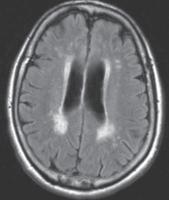

在 CT 上,小血管缺血性疾病表现为小穿支动脉区域皮质下和脑室周围白质的多发性白质低密度影。基底神经节和幕上区域也可见局灶性腔隙(图 5A )。高血压患者常见的自发性出血,一般位于基底节或丘脑。在存在败血症或先天性心脏病的情况下,栓子也会在血管区域之间的边界处产生分水岭梗塞。MRI 显示缺血区域在 T2/FLAIR呈现 高信号(图 5B ))。扩散受限存在于急性期,但在亚急性期和慢性期正常化。

图 5A——小血管缺血性疾病。半卵圆中心水平的平扫 CT 图像显示弥漫性皮质下白质低密度以及代表腔隙的更多局灶性低密度(箭头)

图 5B —小血管缺血性疾病。FLAIR 图像显示多个脑室周围高信号灶。